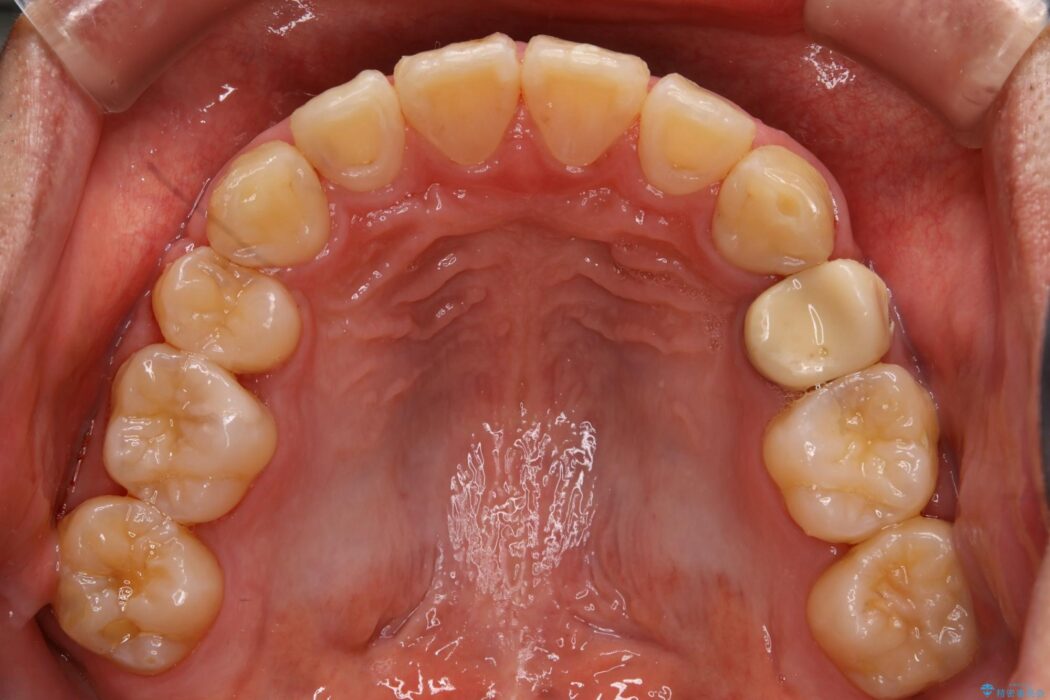

上の歯の出っ歯と下の歯のガタつきが気になるとご来院された患者様です。

出っ歯とガタつきの改善には抜歯が必要と診断し、上下左右第一小臼歯を抜歯することとしました。